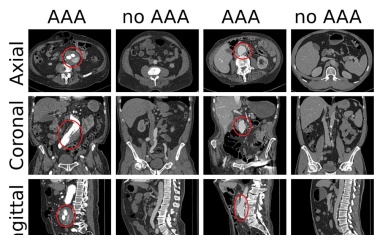

Lebensbedrohliche Erkrankungen der Bauchschlagader sicherer erkennen und schneller behandeln zu können, ist das Ziel des gemeinsamen Projektes DeepRAY der Universitätsmedizin Mannheim (UMM) und der mediri GmbH. Die Prognose der Betroffenen soll damit verbessert und vermeidbare Todesfälle verhindert werden.